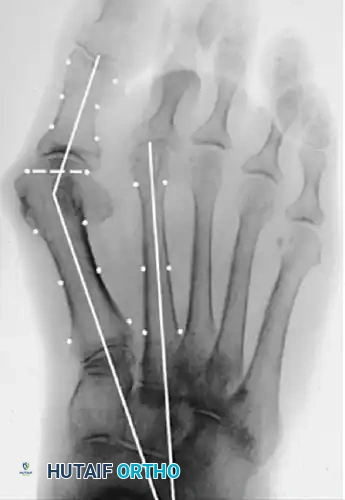

Standard weight-bearing anteroposterior (AP), lateral, and sesamoid axial radiographs are mandatory. Surgical decision-making relies heavily on precise angular measurements.

Key Radiographic Parameters

• Hallux Valgus Angle (HVA): The angle between the longitudinal axes of the first metatarsal and proximal phalanx. Normal is < 15°.

• Intermetatarsal Angle (IMA): The angle between the longitudinal axes of the first and second metatarsals. Normal is < 9°.

• Distal Metatarsal Articular Angle (DMAA): The angle between the articular surface of the first metatarsal head and the longitudinal axis of the metatarsal shaft. Normal is < 10°. An increased DMAA indicates a congruous joint in a valgus position, necessitating a specific intra-articular or extra-articular corrective osteotomy.